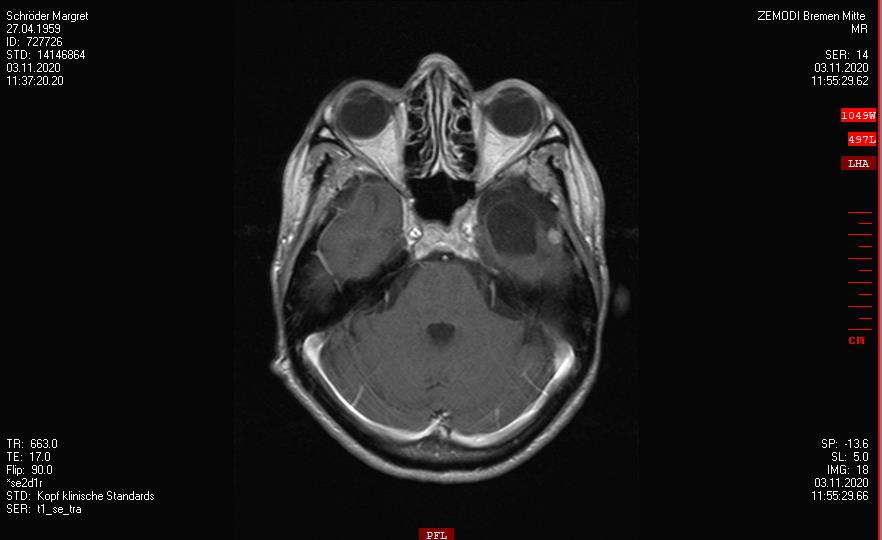

OP - Krankenhaus Bremen-Mitte

Resektion des Keilbeinflügelmeningeoms links

2019-2020

Ein Rezidiv wächst langsam